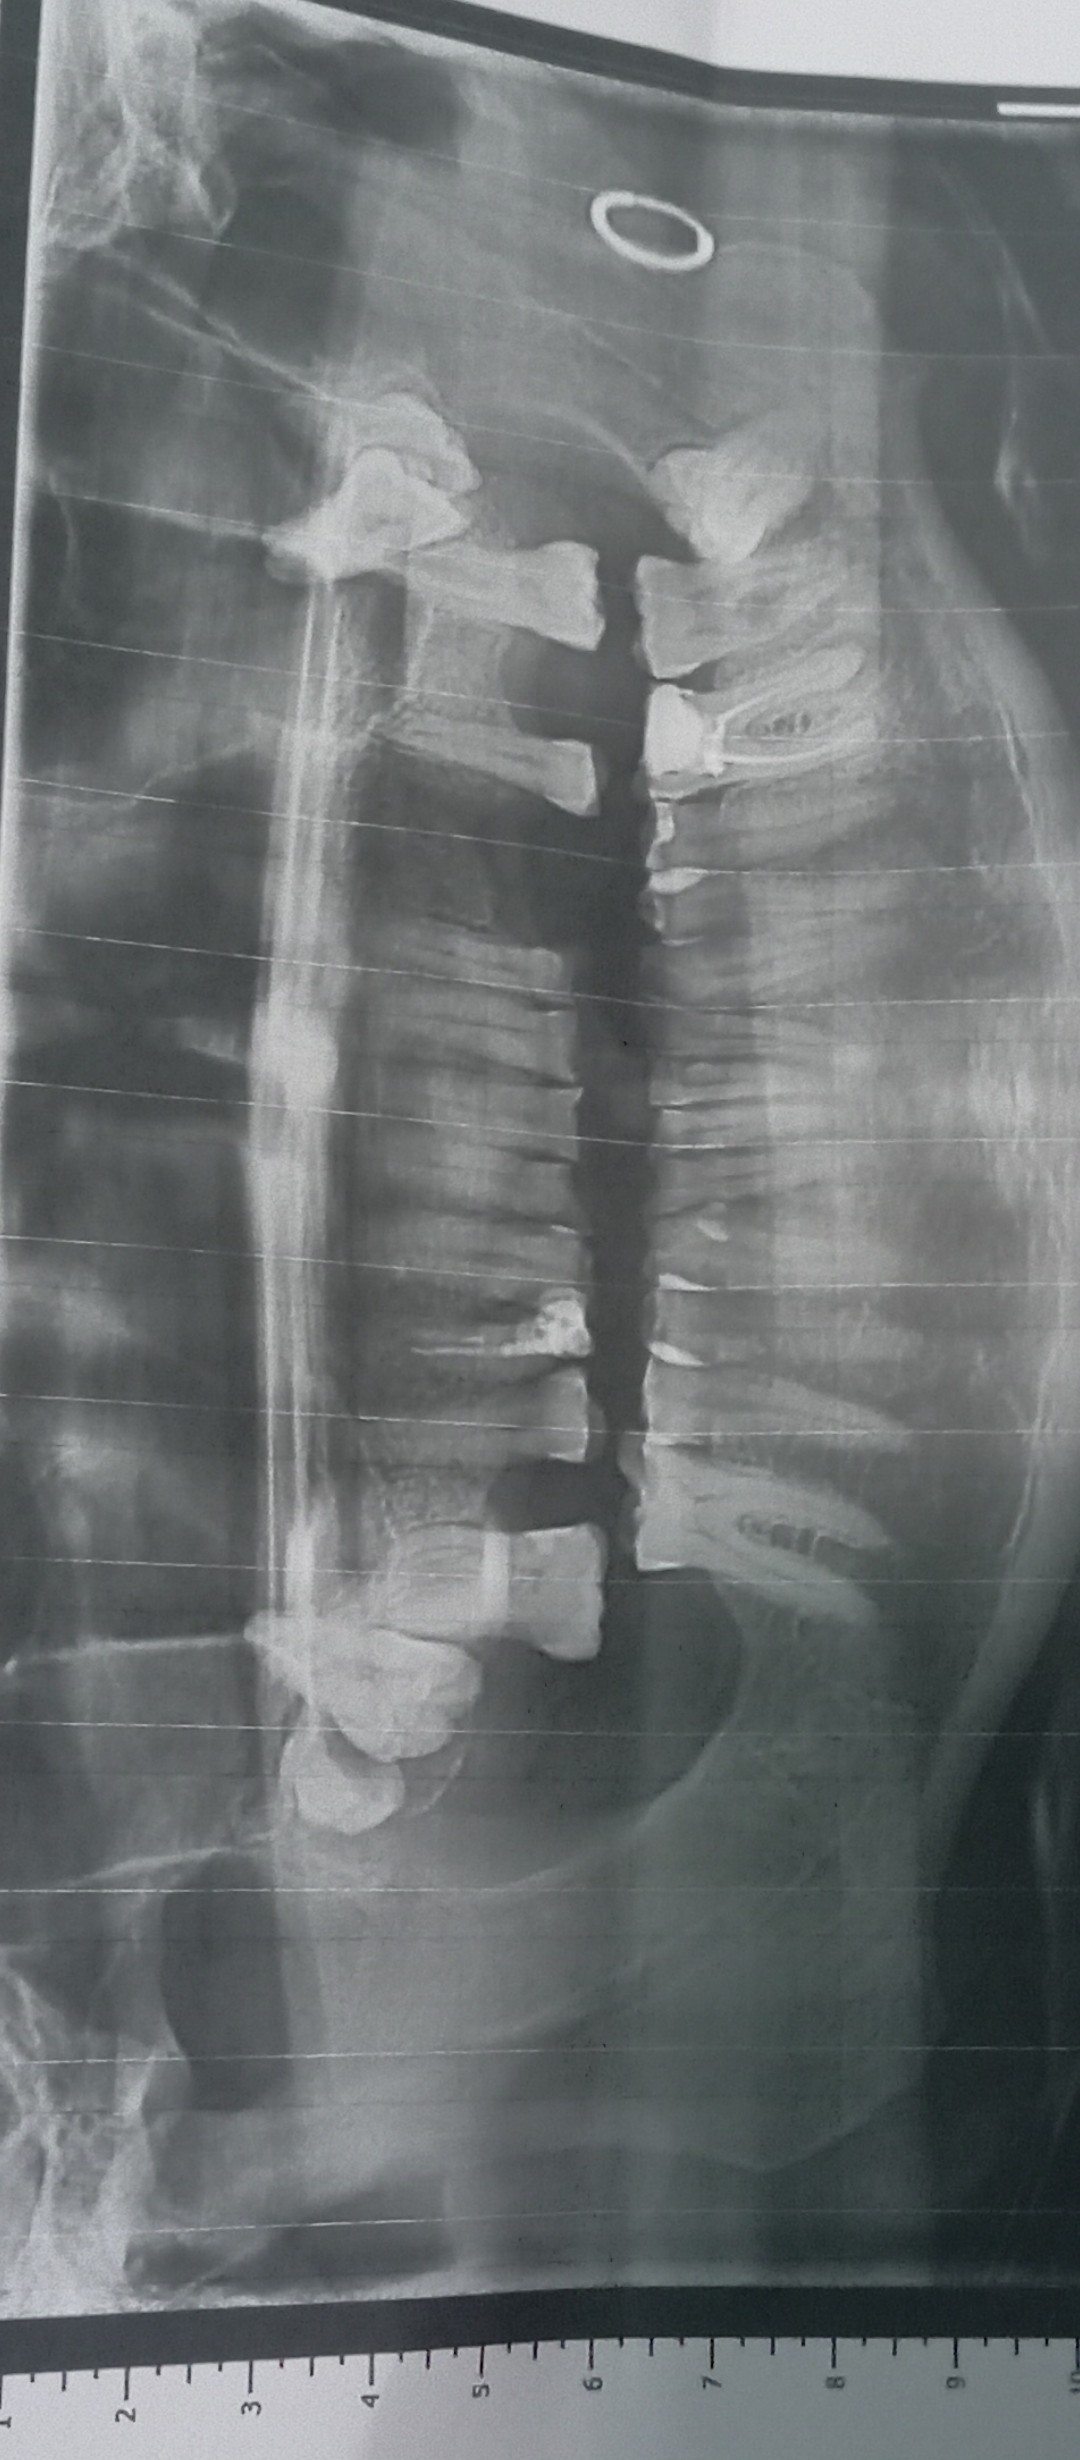

Вітаю, Добрый день. Неделю назад у меня начала болеть десна в нижнем ряду за седьмым зубом. Там как бы ранка Толи трещина и подпухло немного. Та восьмерка седит крепко. Мне 46 доктор говорил шо она уже не выйдет. Так вот через пару дней добавилась боль в шестом или седьмом зубе. Пульсирующая боль. Ночью не спал почти. Утром сегодня поехал к хирургу он удалил шестой зуб так как он плохой на снимке. Теперь я думаю решил ли я проблему, или это будет продолжаться и в е это из-за восьмёрки? Как думаете на снимке есть восполнение которое давало боль? Спасибо

"Теперь я думаю решил ли я проблему, или это будет продолжаться и в е это из-за восьмёрки? Как думаете на снимке есть восполнение которое давало боль? " - Есть воспаление, зуб удалили правильно. Но боль, которую вы испытывали, скорее всего, была связана с воспалением десны над восьмым зубом, так как всё от туда начиналось.

Я ещё не пойму что болит. Было сложное удаление. Там на снимке киста была на шестерка? А семёрка на снимке нормально?

"Там на снимке киста была на шестерка? " - Не киста, но гранулема, т. е. очаг хронического воспаления вокруг верхушки корня.

"А семёрка на снимке нормально? " - Да, нормально.

Добрый день. Позавчера был в челестно лицевой областной с сильной болью. Альвиолит. Почистили все. Выписали антибиотик моксиклав и доксициклин. Болит ужасно сильно соседний зуб пятый. Как при пульпите. На нем есть темное пятнышко но свиду зуб нормальный. Я не знаю шо делать уже с ним. Хирург сказал что зуб хороший. Но он же сильно выражено болит. Даже лунка не так болит. Как Вы видите на снимке он норм?